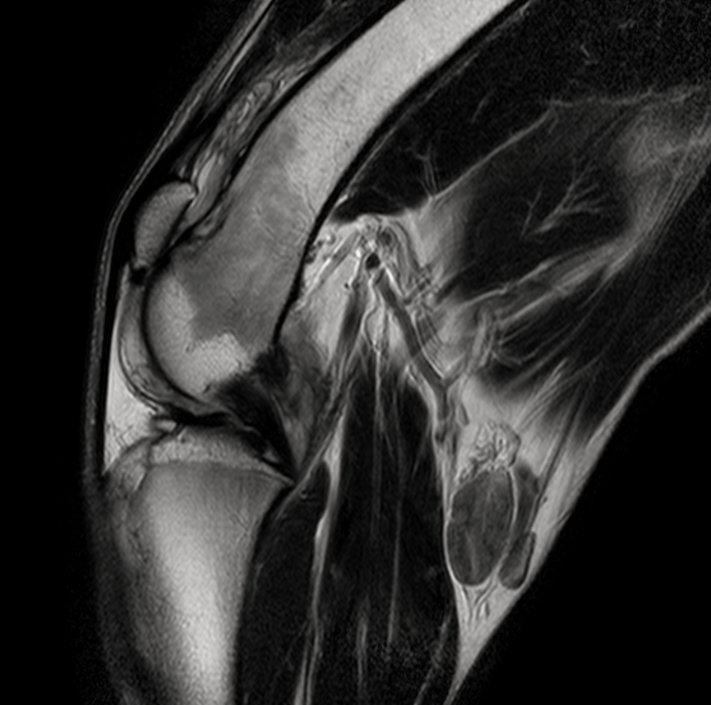

МРТ исследования проводятся на аппарате высокого качества Phillips Intera с напряженностью магнитного поля 1,5 Тесла. Позволяет максимально точно визуализировать анатомические структуры одинаково хорошо животному от 200г до 200кг

- Проведение мрт животному

- Повторяющейся хромоте,

- Подозрении на новообразование, когда установить диагноз другими методами невозможно.